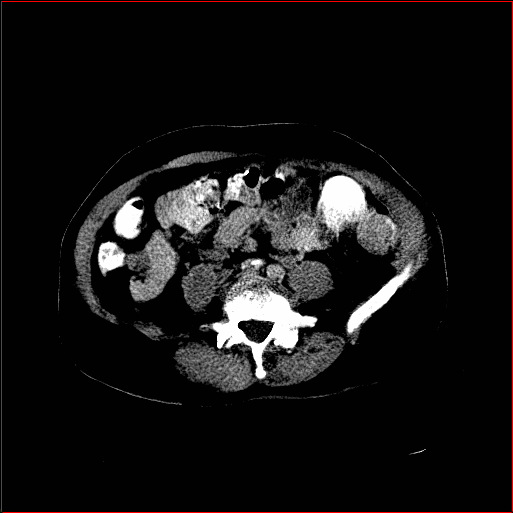

HA-GAN (sun2022hierarchical)

GenerateCT (hamamci2024generatect)

MedSyn (xu2024medsyn)

MAISI-DDPM (guo2025maisi)

MAISI-v2

Figure 2: Qualitative comparison across axial (top row), sagittal (middle row), and coronal (bottom row) views. Columns correspond to different methods. MAISI-DDPM and MAISI-v2 in this figure are unconditional synthesis which do not use ControlNet or segmentation maps.

Qualitative Evaluation:

Figure 2 presents representative slices from the axial, sagittal, and coronal planes. GenerateCT (hamamci2024generatect) is a 2D model, so it lacks inter-slice consistency, leading to poor image quality in the sagittal and coronal views. MedSyn (xu2024medsyn) produces noticeably blurry results with mosaic-like artifacts, such as region inside the red box. HA-GAN (sun2022hierarchical) generates visually sharp images but with mosaic-like artifacts, such as region inside the red box. Also, its voxel spacing is not available, which limits its applicability in real-world medical imaging tasks. Moreover, all three methods are restricted to synthesizing small anatomical regions. In contrast, both MAISI and MAISI-v2 are capable of generating high-quality 3D volumes that span larger body regions while preserving fine anatomical details and realistic structure.